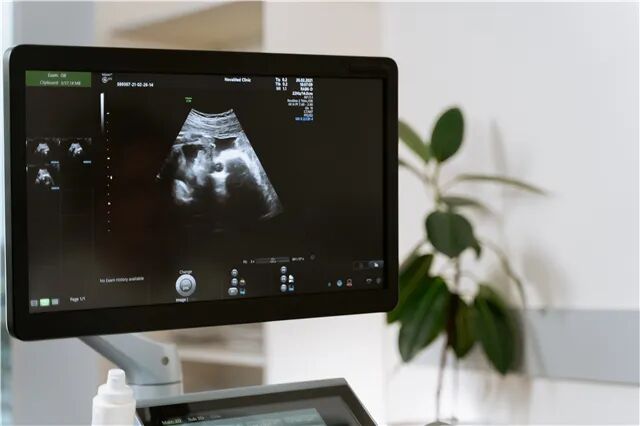

胚胎停育(embryo damage)是指早孕期由于受精卵缺陷、母体自身因素或外界等不利因素影响而导致的胚胎死亡现象。超声检查结果常表现为枯萎卵,有胚芽无心管搏动,有形态不规则的胚芽或胎儿存在于孕囊。

一是受精卵着床后未发育出胎芽,彩超表现为孕7周后仍未见胎芽只见一空(胎)囊。

二是曾有胎芽发育但不久停育死亡,超声结果胎囊中有胎芽但发育明显落后于孕周,同时没有胎心管搏动,胎囊大小符合孕周或萎陷变形,称为孕囊枯萎。